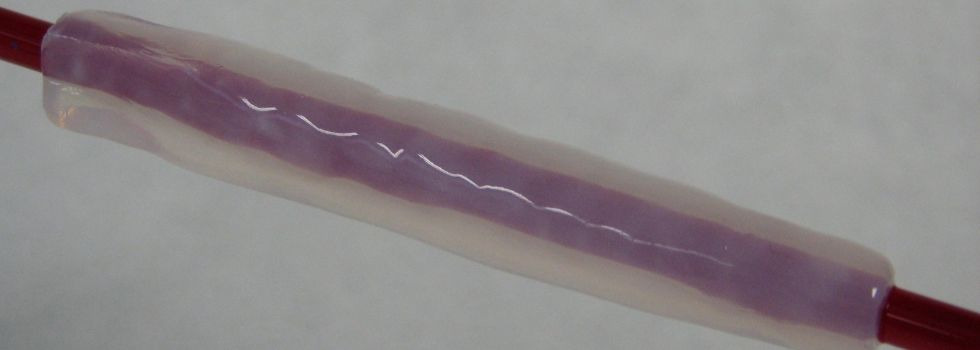

Artificial Bypass - Tissue Engineering in Cardiac Surgery

With a share of more than 50%, bypass surgery represents the largest share in the cardiac surgery portfolio. Every year alone in the US and Germany together… more.